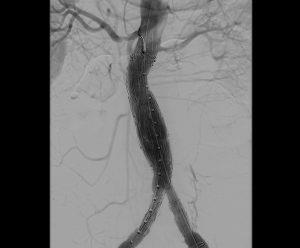

血管撮影検査

腕や足の比較的太い血管からカテーテルと呼ばれる細い管を入れ、心臓や脳、腹部の血管など選択的に挿入し、その先から造影剤を注入し、造影された血管の走行状態、病変まで撮影、治療を行います。

心臓用、頭部用、腹部用(+IVRCT)、ハイブリッド血管撮影装置の4台の装置が稼働しており、緊急検査・治療にも対応しています。